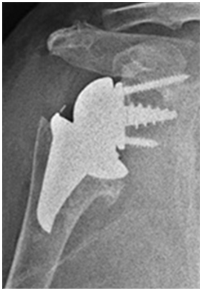

인공관절수술 후